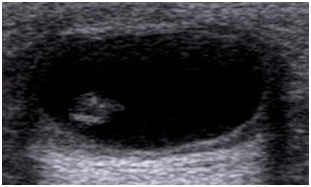

Ultrasound examination of the sub hyoid region showed a 3.3x2.2cm cystic lesion in the subcutaneous plane and an eccentrically placed echogenic solid nodule with curved structure within it with surrounding inflammatory tissue changes. Findings suggested a possibility of cysticercosis (Figure 2). Furthermore, stool and blood Enzyme Linked Immuno Sorbent Assay (ELISA) were ordered and were normal and positive for Cysticercosis antibody respectively.

Figure 2 Ultrasonography of the neck region showing a well-defined thick walled 3.3x2.2cm anechoic cystic lesion in the subcutaneous plane with posterior acoustic enhancement and an eccentrically placed echogenic solid nodule within it with surrounding inflammatory tissue changes.

Ultrasonography is the most reliable initial diagnostic modality of choice for a soft tissue swelling. An eccentrically located cyst with a hyper echoic scolex within and surrounding mild edema is the usual appearance of soft tissue cysticercosis on ultrasonography.